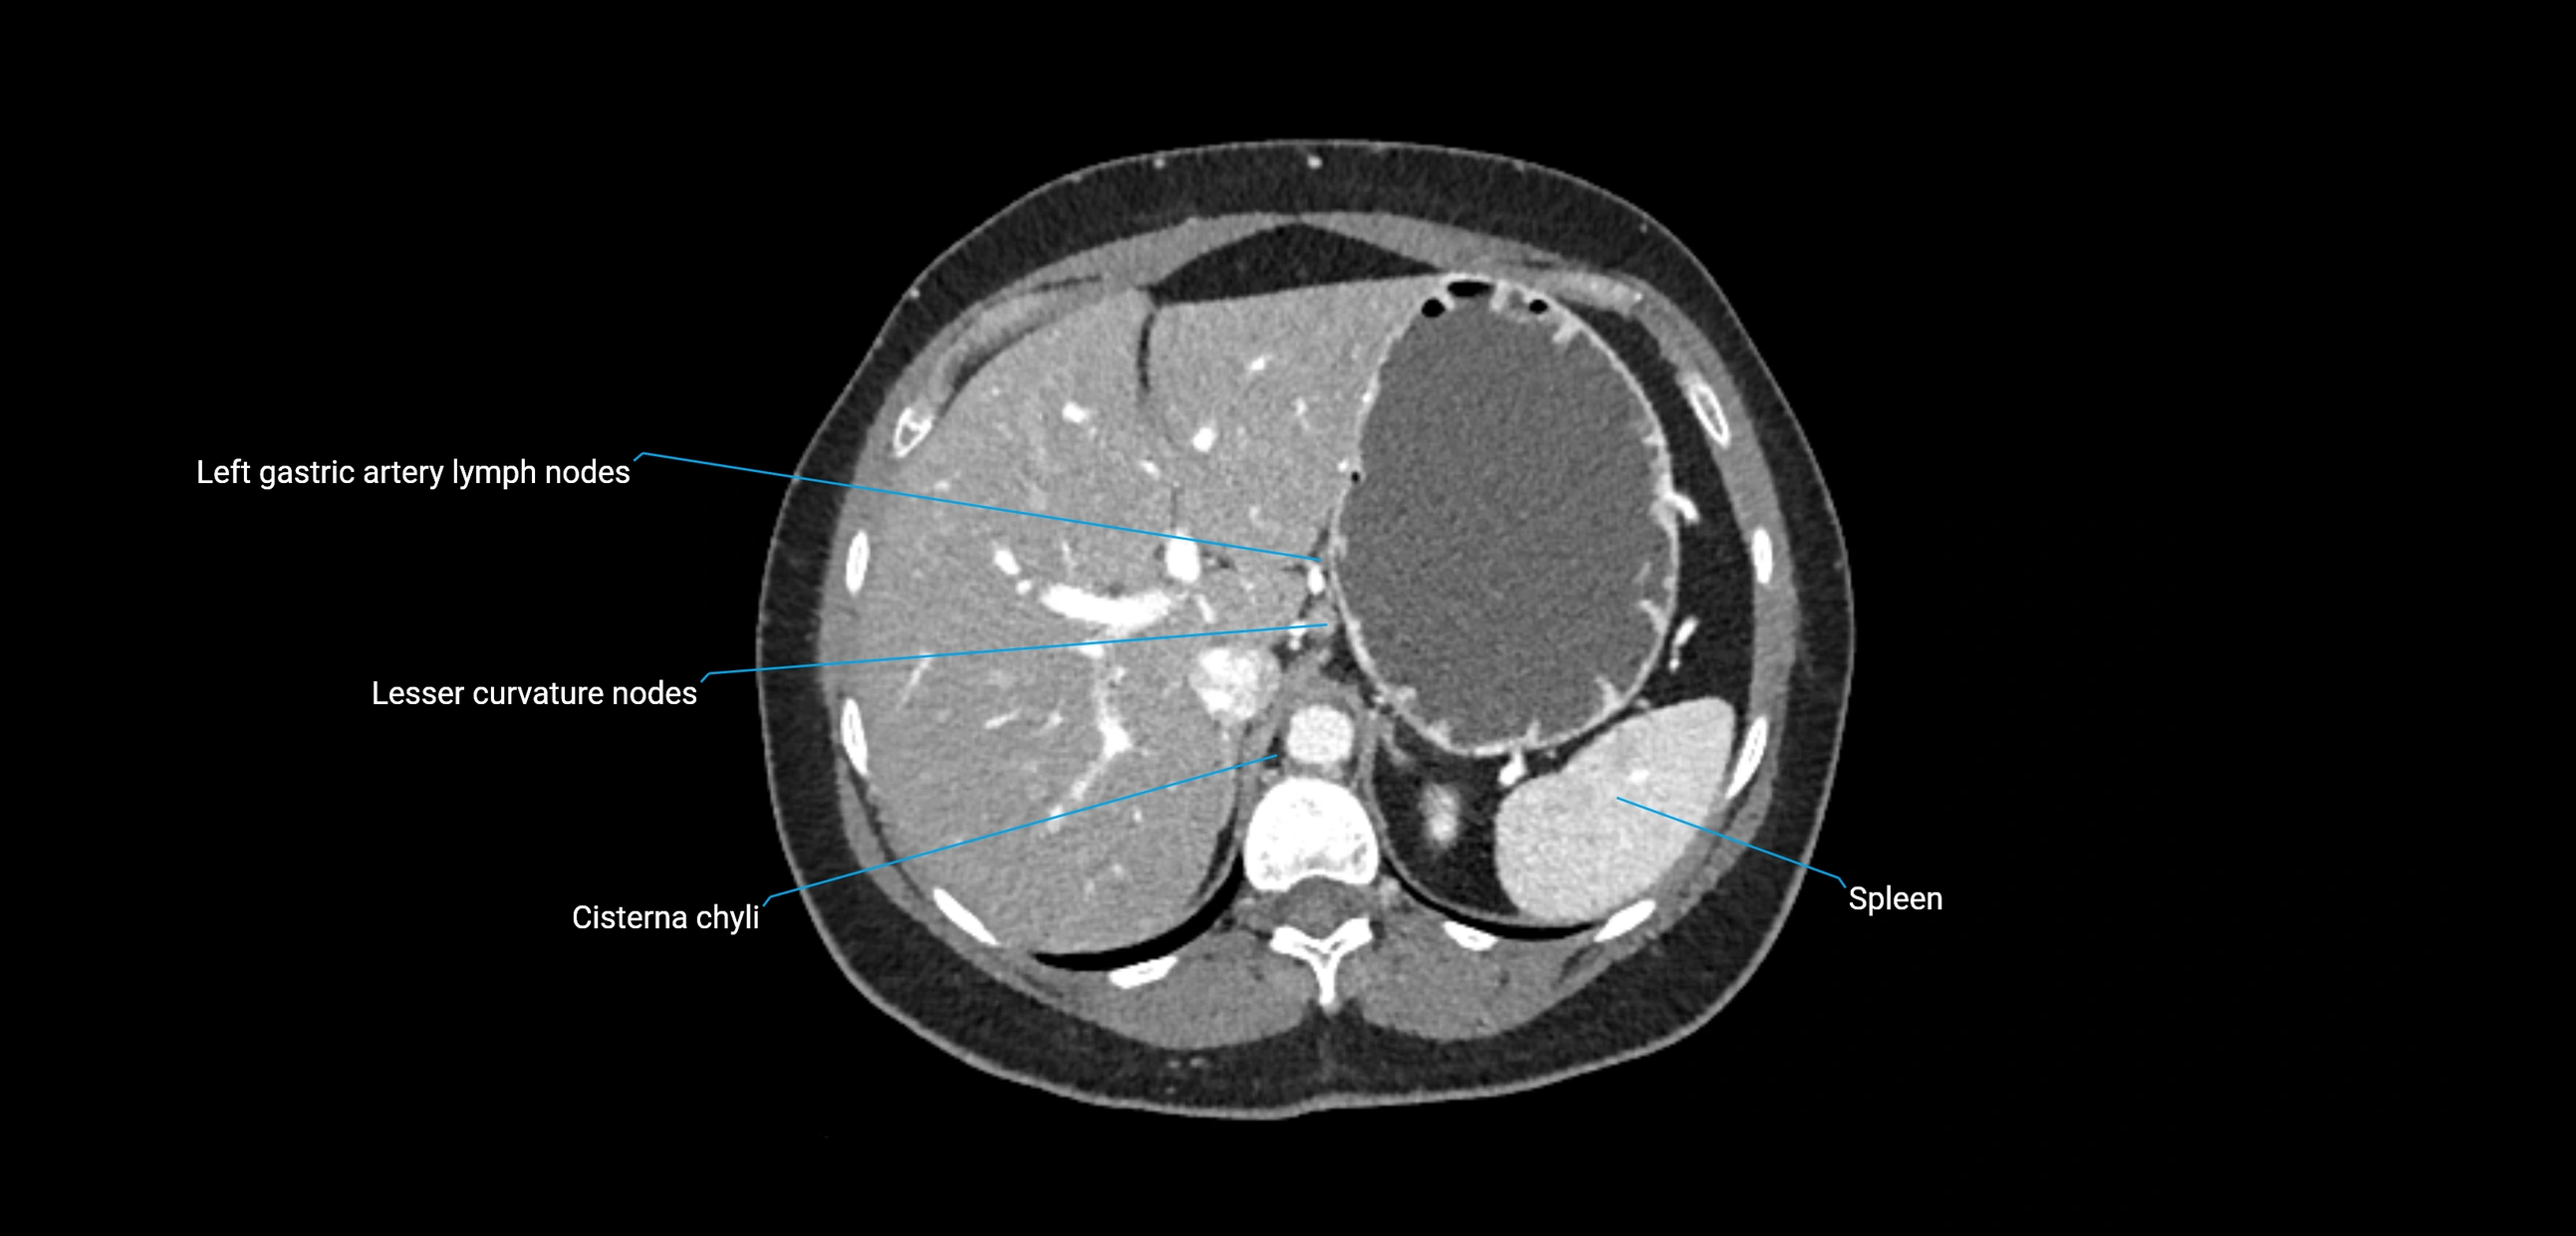

CT Appearance

CT Pre-Contrast:

• Nodes appear as soft-tissue density nodules adjacent to the aorta and IVC

• Calcification may be seen in chronic infections (e.g., tuberculosis)

CT Post-Contrast:

• Normal nodes enhance homogeneously

• Malignant nodes may show heterogeneous enhancement, central necrosis, or conglomerate formation

• Size >1 cm short axis is suspicious, though morphology and distribution are equally important